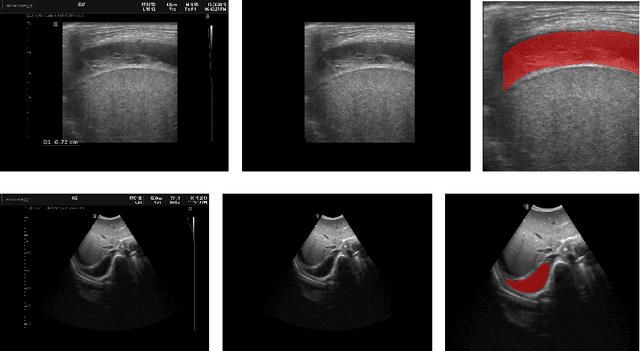

Abstract:In many low-to-middle income (LMIC) countries, ultrasound is used for assessment of pleural effusion. Typically, the extent of the effusion is manually measured by a sonographer, leading to significant intra-/inter-observer variability. In this work, we investigate the use of deep learning (DL) to automate the process of pleural effusion segmentation from ultrasound images. On two datasets acquired in a LMIC setting, we achieve median Dice Similarity Coefficients (DSCs) of 0.82 and 0.74 respectively using the nnU-net DL model. We also investigate the use of coordinate convolutions in the DL model and find that this results in a statistically significant improvement in the median DSC on the first dataset to 0.85, with no significant change on the second dataset. This work showcases, for the first time, the potential of DL in automating the process of effusion assessment from ultrasound in LMIC settings where there is often a lack of experienced radiologists to perform such tasks.

Abstract:Sickle Cell Disease (SCD) is one of the most common genetic diseases in the world. Splenomegaly (abnormal enlargement of the spleen) is frequent among children with SCD. If left untreated, splenomegaly can be life-threatening. The current workflow to measure spleen size includes palpation, possibly followed by manual length measurement in 2D ultrasound imaging. However, this manual measurement is dependent on operator expertise and is subject to intra- and inter-observer variability. We investigate the use of deep learning to perform automatic estimation of spleen length from ultrasound images. We investigate two types of approach, one segmentation-based and one based on direct length estimation, and compare the results against measurements made by human experts. Our best model (segmentation-based) achieved a percentage length error of 7.42%, which is approaching the level of inter-observer variability (5.47%-6.34%). To the best of our knowledge, this is the first attempt to measure spleen size in a fully automated way from ultrasound images.